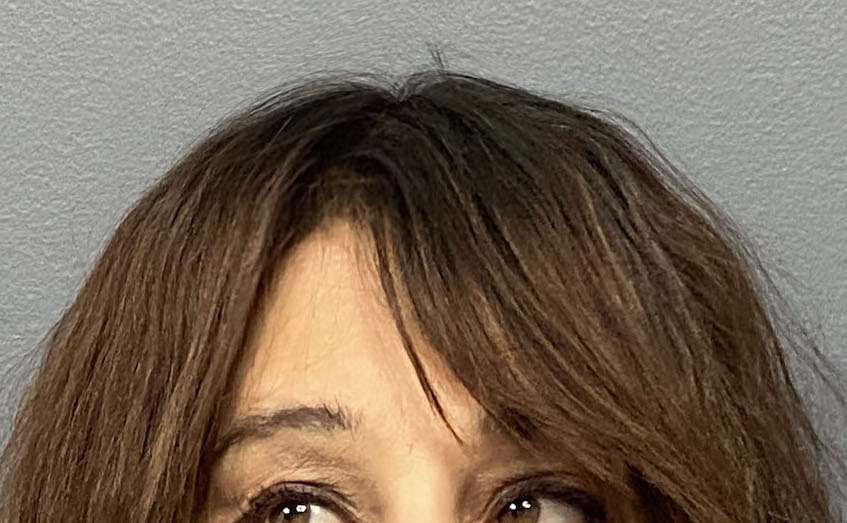

Patient 45

Desire for reduction in height of top of head.

Top of head skull reduction by removal of the outer cortical bone layered by a grid burring technique.

Desire for reduction in height of top of head.

Top of head skull reduction by removal of the outer cortical bone layered by a grid burring technique.